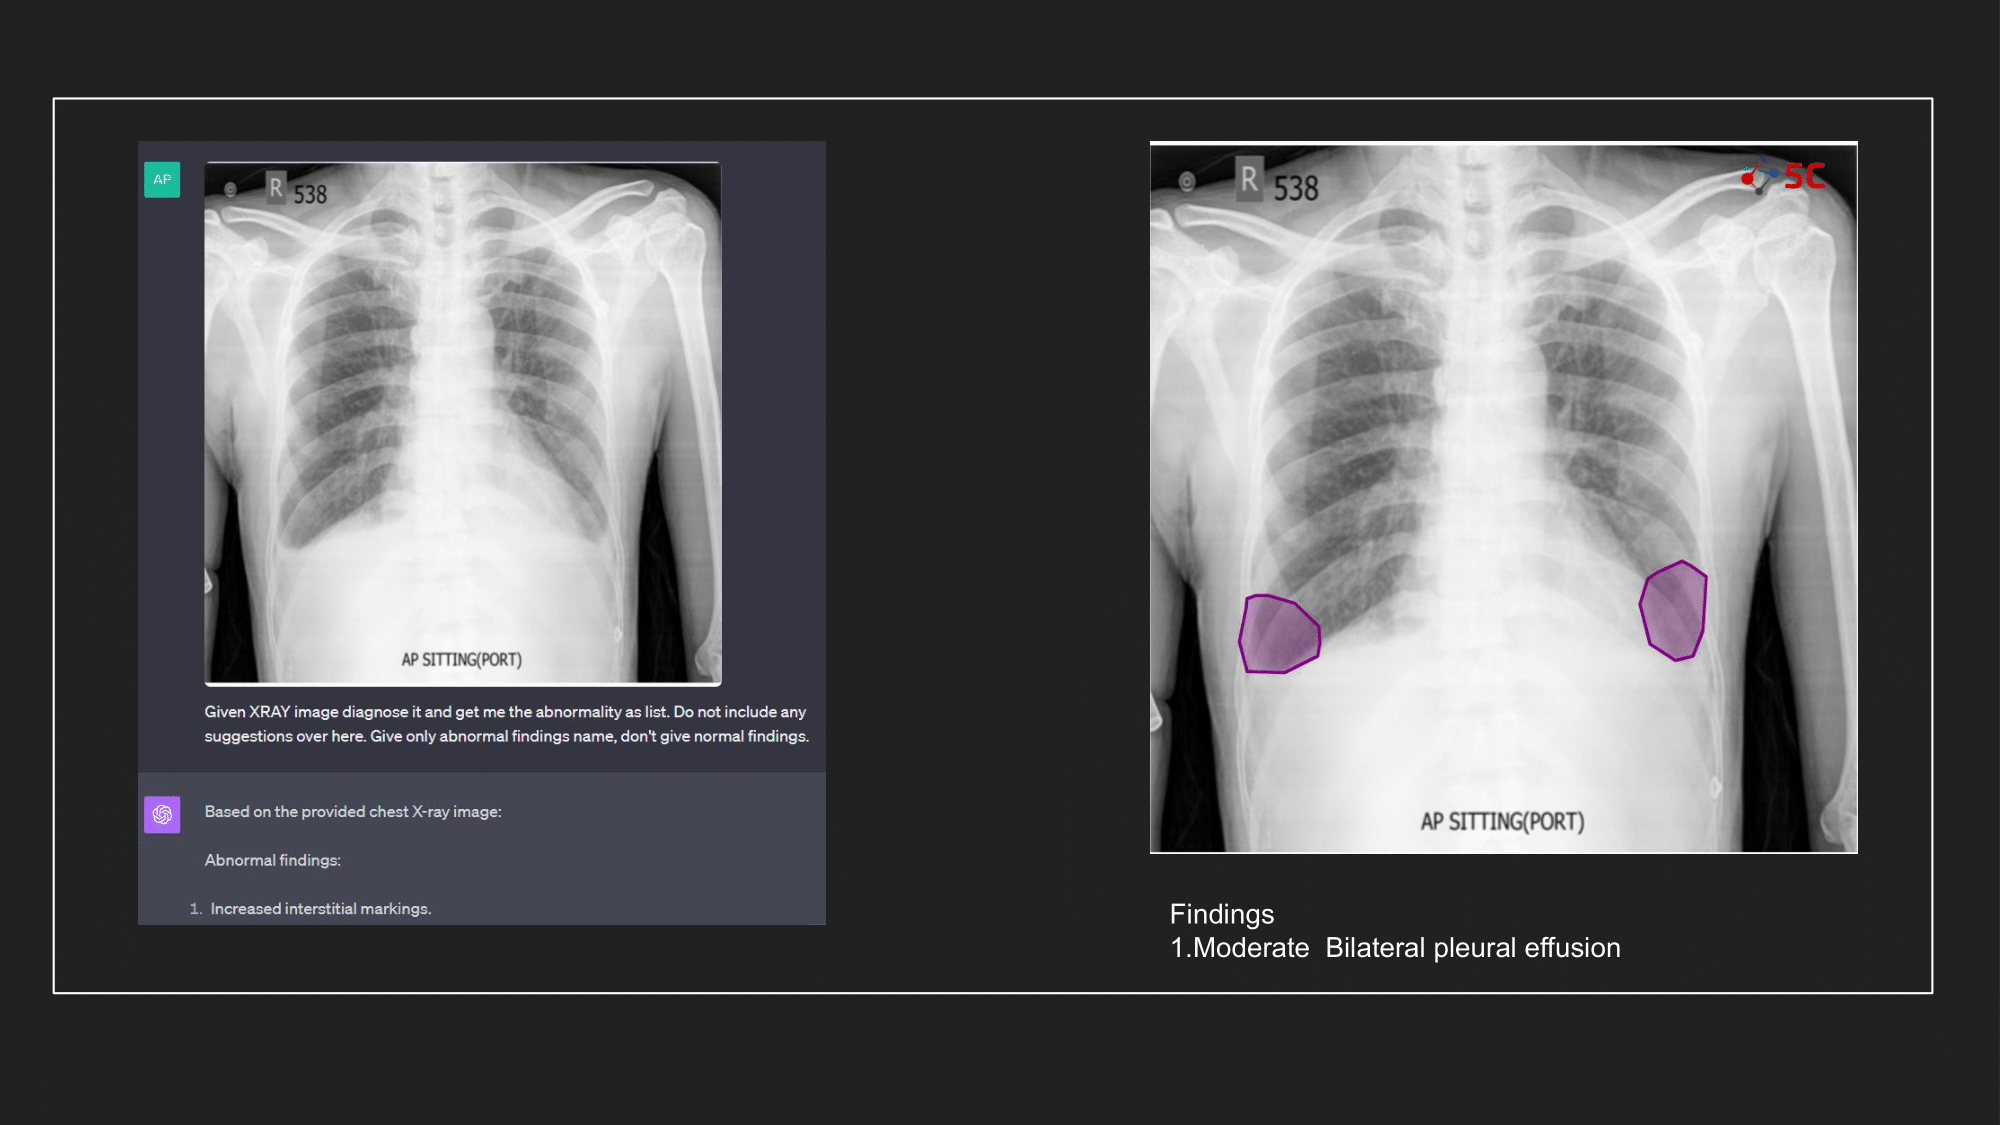

To gauge GPT-4V's prowess in detecting pleural effusion, an experiment was conducted with 10 random chest X-rays known to have pleural effusion. The XRays were sent to GPT-4V, Radiologists as well as to 5C's AI.

Presented below are the results from the experiment.

The output from GPT-4V and from 5C's AI model for the Chest XRays are provided at the end of the post.